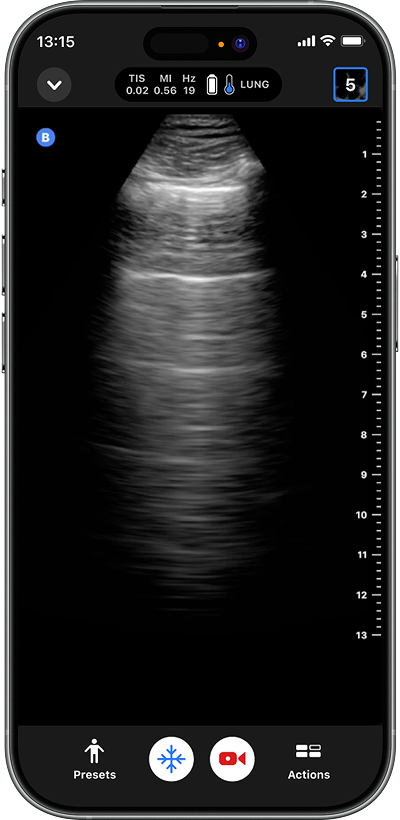

Perform bedside assessment for pneumonia, CHF, asthma exacerbation, or pneumothorax.